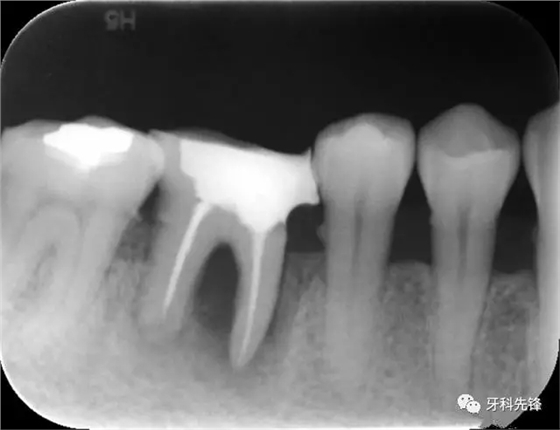

圖8治療術(shù)后X光片